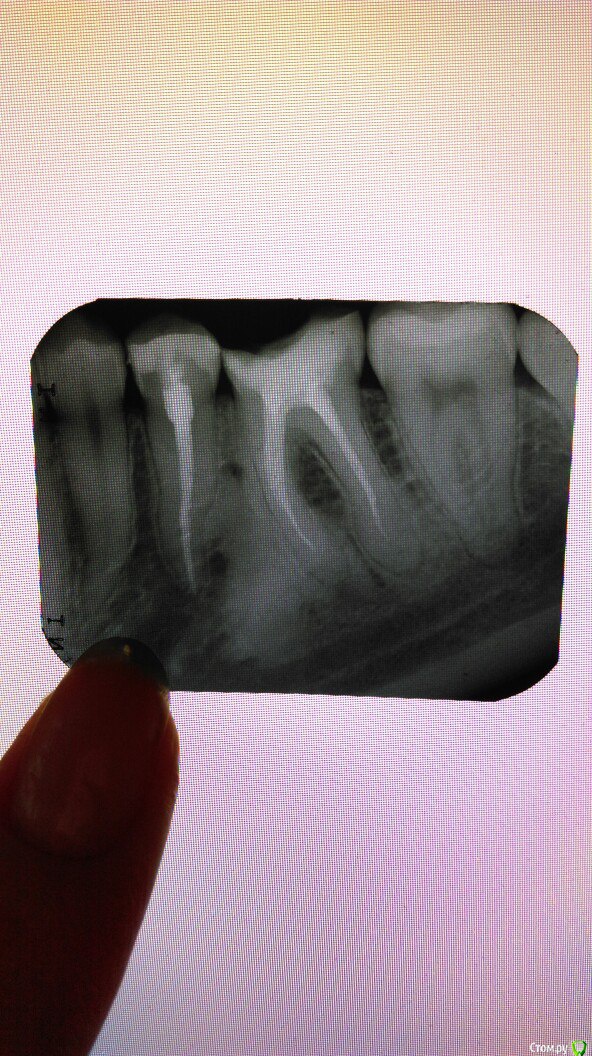

Civil Опубликовано 10 июня, 2016 Поделиться Опубликовано 10 июня, 2016 Пришла с острой болью в клинику, попала к врачу о котором ничего не знаю, путем вскрытия 2х зубов под пломбами оказался кариес и пульпит. второй месяц делаем эти 2 зуба. врач мне не объясняет, что именно мы делаем, но после каждого вмешательства зуб болит, и временами появляется сильная "стреляющая" боль. данный снимок последний, врачу не понравился, сказал придти опять. я устала от боли и от хождений туда сюда (около 10 раз была на осмотрах-каких то вмешательств в зуб-сверлений). У мужа возникает мысль, что такой затянутый процесс -не выкачка ли это денег?Хочу попросить вас посмотреть снимок (если в таком качестве что-то видно) и прокомментировать качество пломбировки каналов, что не так? Ссылка на комментарий

Павел7809 Опубликовано 10 июня, 2016 Поделиться Опубликовано 10 июня, 2016 Зуб , мягко сказать непростой, будем надеяться что успокоится, а если нет то удаление будет не самым простым. Ссылка на комментарий

Civil Опубликовано 11 июня, 2016 Автор Поделиться Опубликовано 11 июня, 2016 Зуб , мягко сказать непростой, будем надеяться что успокоится, а если нет то удаление будет не самым простым. да, сказали там 4 канала. намучилась с ним уже. а канал левого зуба нормально запломбирован? Ссылка на комментарий

Ker Опубликовано 11 июня, 2016 Поделиться Опубликовано 11 июня, 2016 а канал левого зуба нормально запломбирован?Да, сделан хорошо. Ссылка на комментарий